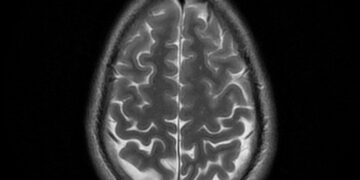

Read moreGreen Tea’s Role In Fighting Dementia-Linked Brain Lesions A recent study from Japan has strengthened the evidence supporting the health...

Read moreSleep Aid Found Sabotaging The Brain A recent study has raised concerns about the effects of sleep aids, particularly zolpidem...

Read moreGrowing Threat Set To Double By 2060 A recent study has revealed that the risk of dementia among seniors is...

Read moreShocking Science Of Sleep Medications A new study suggests that Ambien, a popular sleep aid, could contribute to the buildup...

Read moreThe Common Habit Wrecking Work Productivity Experiencing brain fog or difficulty concentrating due to lack of sleep is a common...